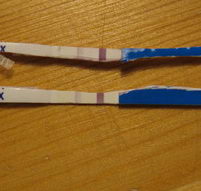

Húha!!! Ez nagyon bíztató! Drukkok!! Amúgy meg miért vársz erősebbet a 12. dpo-n?? 14. dpo előtt nem is érdemes igazán tesztelni. Úgyhogy ez tuti pozitív!!

Drukk!! De nem faldni, ha nem csíkos. 13. dpo még kicsit korai.